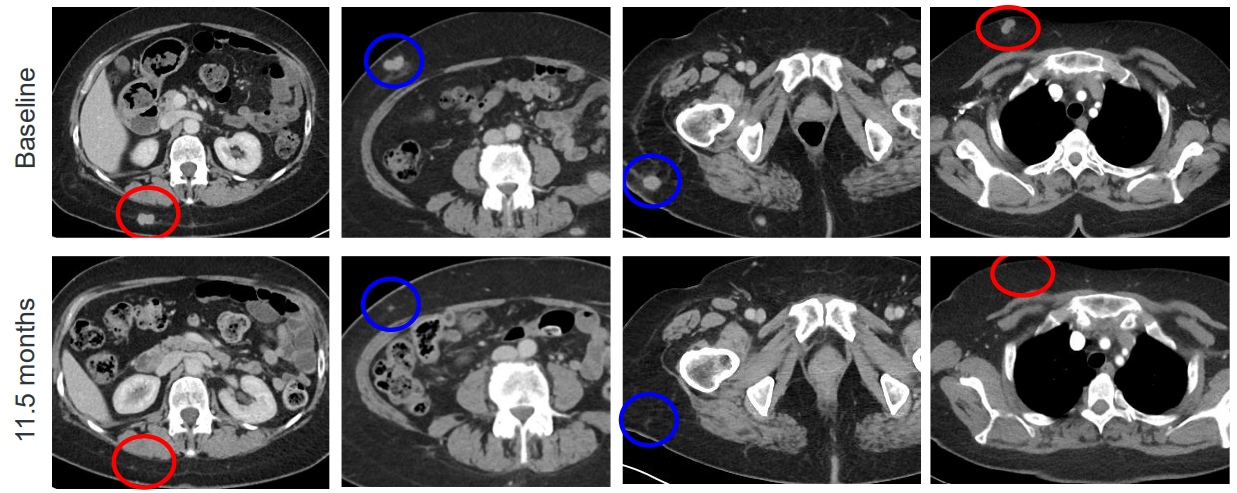

到2022年夏天时,Roberto Romero对于治疗自2015年以来一直与之抗争的黑色素瘤,已经快无计可施了。他之前已经做过几次手术,也接受过多轮药物治疗。但始于他脚趾甲下一个小黑点的癌症仍在继续生长,并已侵入他的器官。